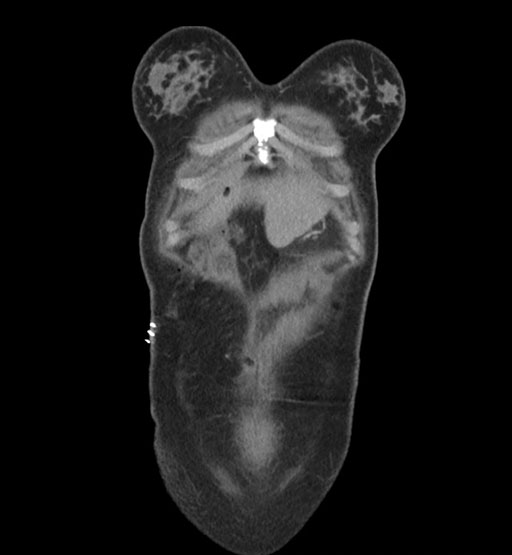

Axial Arterial

Axial Venous